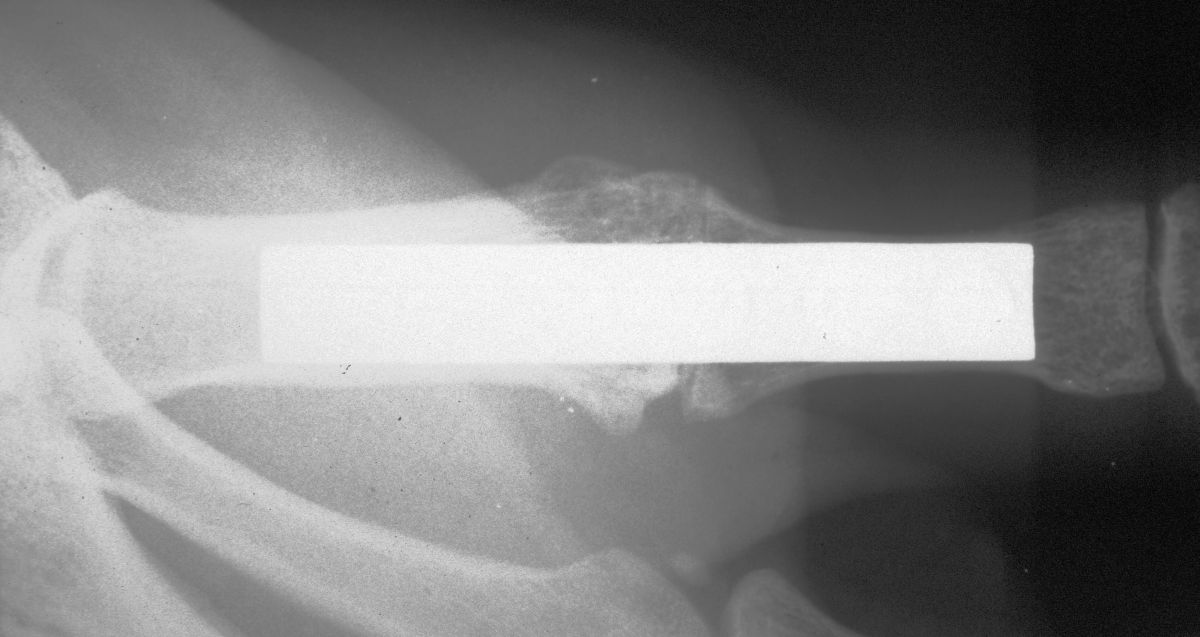

| In this case, 0.045"

K-wires were used for provisional fixation: |

| These were then replaced,

one at a time, with 1.5mm screws. Because of the entry angles, the

countersink bit was used to reduce screw head prominence. |